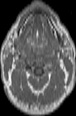

Visible Human male: Sectio transversalis 1213

CT

NMR

Pd T1 T2